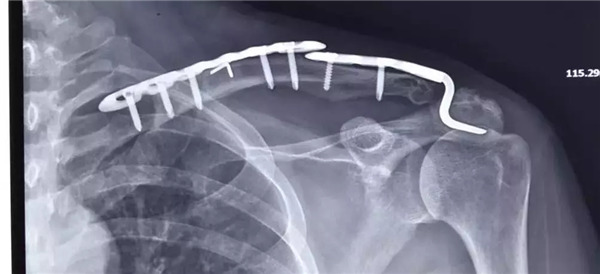

術(shù)后拍片

經(jīng)患者與家屬同意后,羅軍主任手術(shù)團(tuán)隊(duì)成功為患者實(shí)施了左肩鎖關(guān)節(jié)復(fù)位Y型Endobutton固定系統(tǒng)固定術(shù)。手術(shù)只用50分鐘時(shí)間。術(shù)后X片復(fù)查顯示肩鎖關(guān)節(jié)脫位完全復(fù)位,術(shù)后第二天楊女士在康復(fù)醫(yī)師指導(dǎo)下開始進(jìn)行左肩關(guān)節(jié)功能鍛煉,楊女士左肩部疼痛明顯減輕,左肩關(guān)節(jié)可抬起、前舉,功能較術(shù)前明顯改善,楊女士大約再經(jīng)過3-4周康復(fù)訓(xùn)練左肩關(guān)節(jié)功能可恢復(fù)正常。